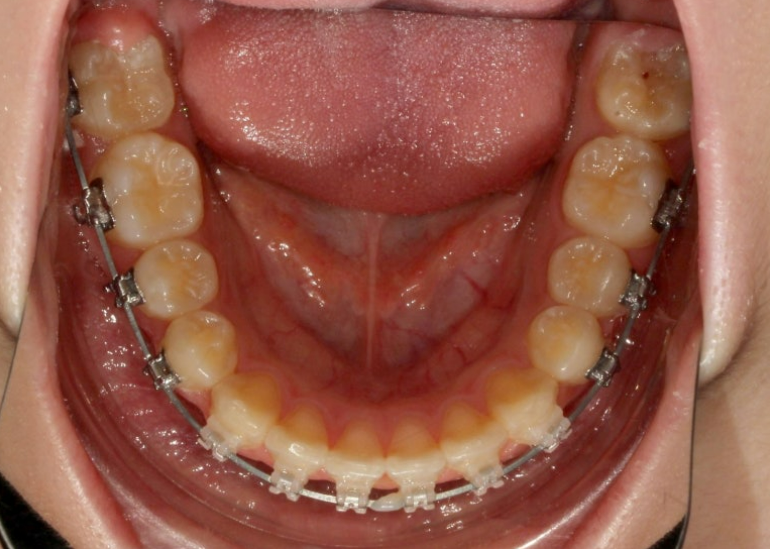

25.06

중심선은 잘 맞습니다.

유난히 커보이던 앞니는 돌출이 해소되고 가지런해지면서 누명을 벗었습니다.

교합은 좋습니다.

간혹 작은어금니 발치교정은 4개를 빼야 교합이 맞지 않나에 대한 질문을 듣는데 위에만 돌출인 경우 위에만 2개 빼는 교정도 좋은교합으로 마무리 되는 교정이랍니다.

그런데 파란화살표에 교정 중 양치가 잘 안되던 부분에 하얀 자국이 보이시죠. 브라켓이 붙어있던 네모모양을 제외한 주변이 초기충치로 얼룩덜룩 해진 모습입니다.

앞으로 관리가 잘 된다면야 큰 문제는 없겟지만 일부는 레진치료가 필요합니다.

교정 중 양치가 어려운 브라켓 주변 등은 월진료 올때마다 병원에서 스케일을 매번 하고 불소도포도 하고 있지만 평소에 양치질이 안되면 장사 없습니다.